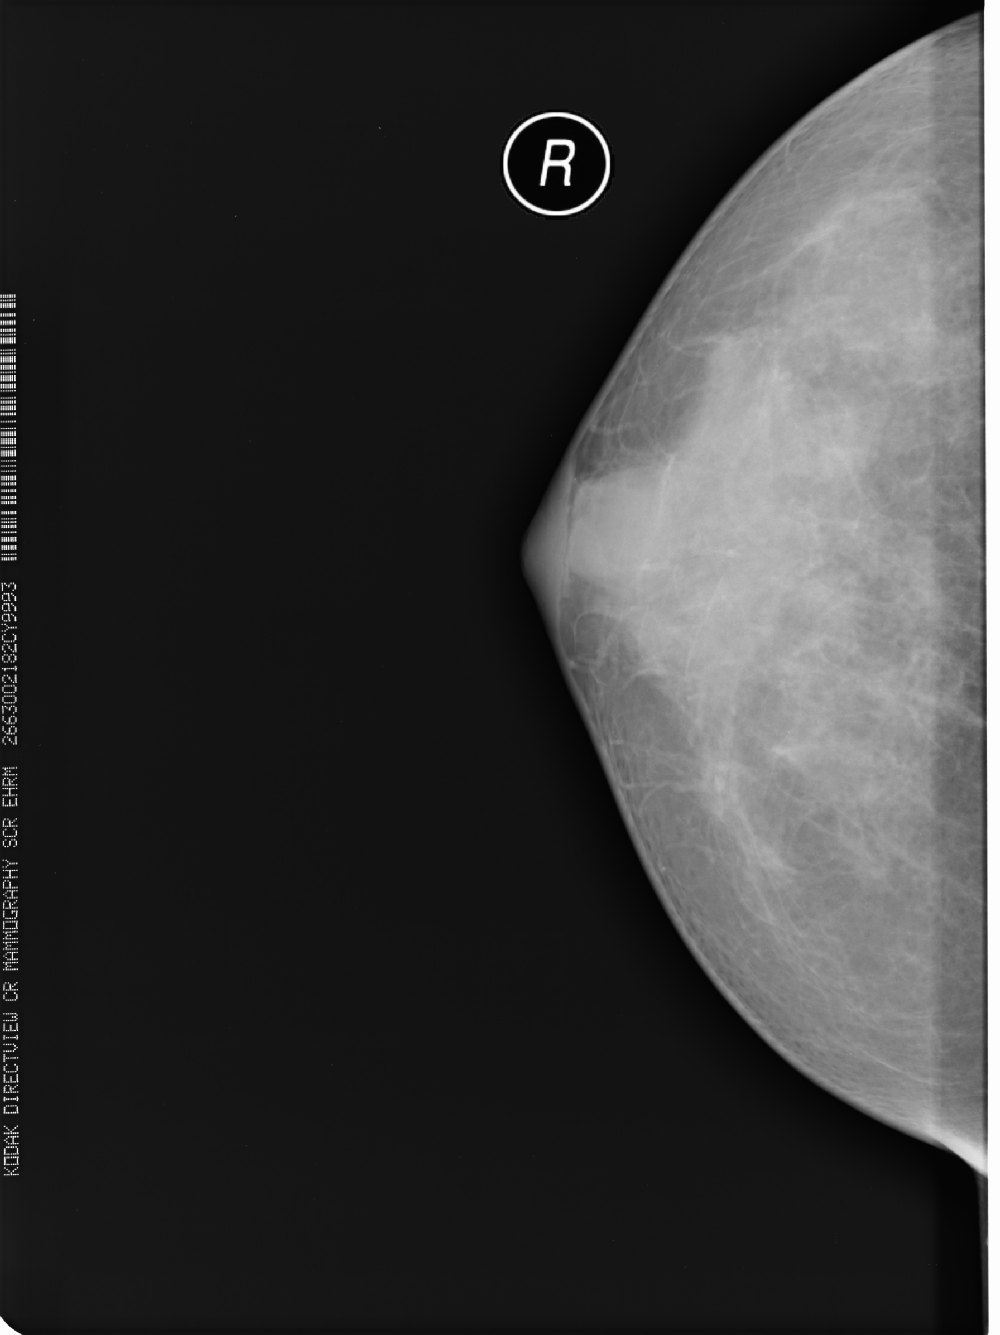

标题: X6857:女,39岁,右乳肿块半年余;三天后公布结果。 [打印本页]

标题: X6857:女,39岁,右乳肿块半年余;三天后公布结果。

所见乳腺内见斑片状高密度影,未见明显占位征象,考虑乳腺小叶增生,结合临床及b超。

右乳腺瘤可能

x6857,女,39岁,右乳肿块半年余;病理结果。

“右”乳纤维腺瘤

纤维腺瘤诊断要点:1,40y以下青年女性2,类圆形肿块,边光、锐利,可有分叶,密度或信号均匀,部分可见粗颗粒样钙化3,增强多呈缓慢渐近性直均匀强化或离心样强化。